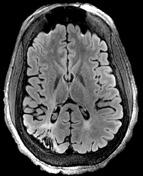

Bistra Iordanova, PhD Research Assistant Professor

We develop multimodal neuroimaging platforms to explore system-level neurovascular and metabolic events during neurogenesis, normal development and neurodegeneration. We are interested in the life of brain cells inside living animals, particularly in the context of neuronal activity, oxygen, glucose and iron metabolism. In pursuit of this knowledge we employ a set of interdisciplinary approaches that combine molecular tools such as optogenetics and reporter protein design with systems-level methods such as Magnetic Resonance Imaging, two-photon and intrinsic optical imaging. We seek to identify accessible molecular targets connected to brain dysfunction. Our work delivers cellularlevel insights into human functional and metabolic imaging.

Long-range Brain Connectivity

Vascular Deficits in Alzheimer’s Disease

The brain has no significant energy storage, and cellular activity evokes adaptive changes in the blood flow to deliver oxygen. We survey the dynamic vascular and metabolic events that develop synergistically in the vessel and the tissue with the amyloid accumulation during Alzheimer’s disease (AD) progression. The aim is to deliver functional and mechanistic roadmap on how these interconnected processes contribute to AD pathogenesis and how they interact with sex, genetic and environmental factors. Our goal is to reveal which events lay at the origin of initial brain dysfunction in order to provide early diagnostic markers for AD as well as suitable targets for intervention.

Cortico-cortical interactions are inherently difficult to study. Using optogenetic tools, optical and functional MR brain imaging we explore the neurovascular activity that drives the transcallosal interaction of left and right brain and elucidate the observed variability in human functional imaging. These findings have significant implications in stroke recovery, investigating the spread of seizures from one side of the brain to the other and bilateral control of brain-machine interfaces.

Metalloprotein-based MRI

We combine molecular engineering and MRI to modulate contrast in brain cells via the expression of novel iron-binding, paramagnetic metalloproteins in the ferritin family. Following transgene expression, the ferritin shells sequester physiologically available iron, and biomineralization of the ferritin core renders the complex paramagnetic, producing MRI contrast. By combining an MRI reporter with a cellspecific expression, a multitude of applications exist. For example, we can track cell migration after neurogenesis. More recently, we have employed the same MRI approaches optimized for iron imaging to evaluate iron accumulation in models of Alzheimer’s disease.